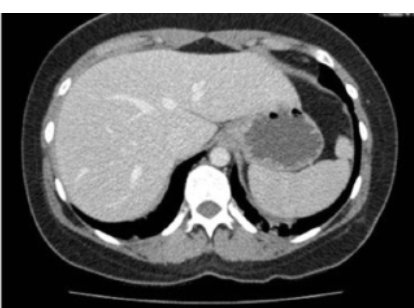

12

A

Mediastinal